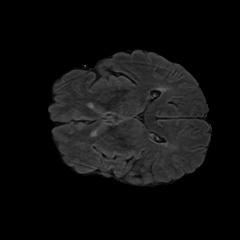

Current unsupervised anomaly localization approaches rely on generative models to learn the distribution of normal images, which is later used to identify potential anomalous regions derived from errors on the reconstructed images. However, a main limitation of nearly all prior literature is the need of employing anomalous images to set a class-specific threshold to locate the anomalies. This limits their usability in realistic scenarios, where only normal data is typically accessible. Despite this major drawback, only a handful of works have addressed this limitation, by integrating supervision on attention maps during training. In this work, we propose a novel formulation that does not require accessing images with abnormalities to define the threshold. Furthermore, and in contrast to very recent work, the proposed constraint is formulated in a more principled manner, leveraging well-known knowledge in constrained optimization. In particular, the equality constraint on the attention maps in prior work is replaced by an inequality constraint, which allows more flexibility. In addition, to address the limitations of penalty-based functions we employ an extension of the popular log-barrier methods to handle the constraint. Comprehensive experiments on the popular BRATS'19 dataset demonstrate that the proposed approach substantially outperforms relevant literature, establishing new state-of-the-art results for unsupervised lesion segmentation.